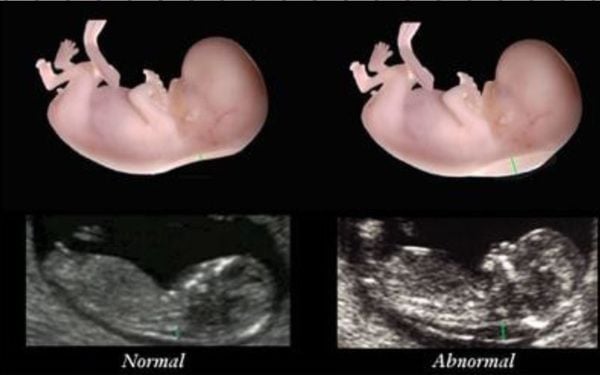

The nuchal translucency test measures the nuchal fold thickness. This is an area of tissue at the back of an unborn baby's neck. Measuring this thickness helps assess the risk for Down syndrome and other genetic problems in the baby.

Your health care provider uses abdominal ultrasound (not vaginal) to measure the nuchal fold. All unborn babies have some fluid at the back of their neck. In a baby with Down syndrome or other genetic disorders, there is more fluid than normal. This makes the space look thicker.

A normal amount of fluid in the back of the neck during ultrasound means it is very unlikely your baby has Down syndrome or another genetic disorder.

Nuchal translucency measurement increases with gestational age. This is the period between conception and birth. The higher the measurement compared to babies the same gestational age, the higher the risk is for certain genetic disorders.

More fluid than normal in the back of the neck means there is a higher risk for Down syndrome, trisomy 18, trisomy 13, Turner syndrome, or congenital heart disease. But it does not tell for certain that the baby has Down syndrome or another genetic disorder.

The NT scan measures the clear (translucent) space in the tissue at the back of your baby's neck. (This is the "nuchal translucency.") Babies with abnormalities tend to accumulate more fluid at the back of their neck during the first trimester, causing this clear space to be larger than average.